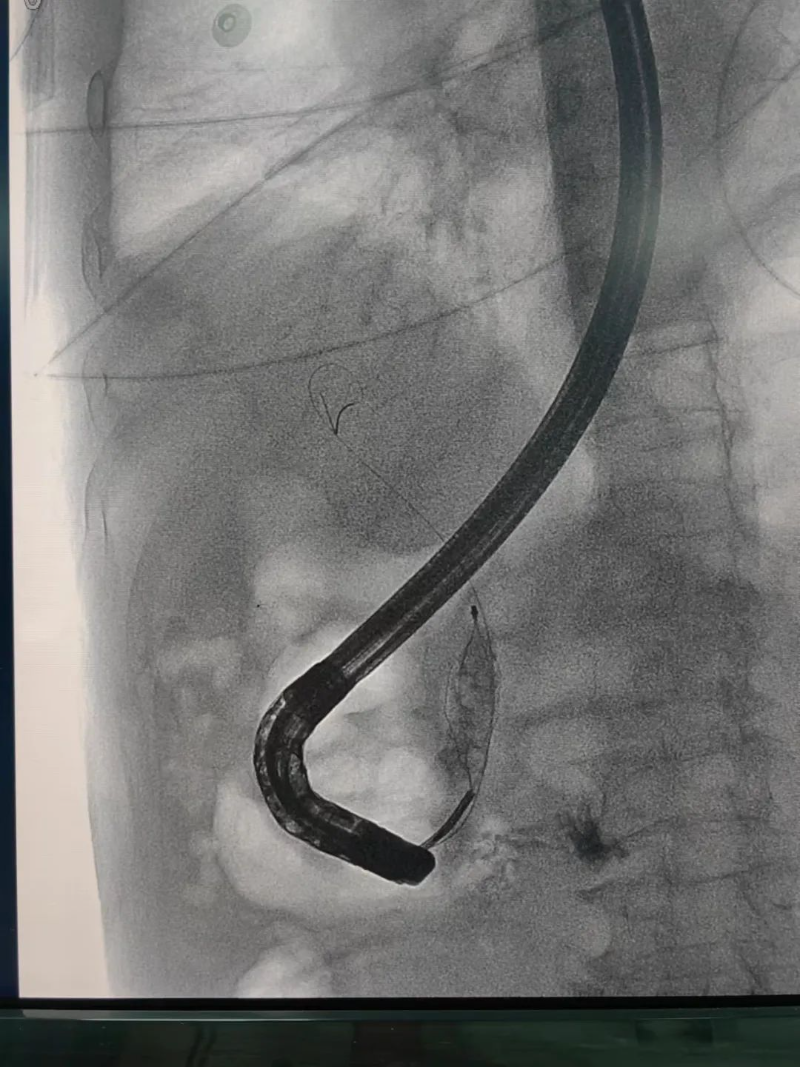

入院后,胡斌立即组织全科进行病例讨论,制定治疗方案。经讨论,一致同意行ERCP(内镜下逆行胰胆管造影技术)解除胆道梗阻。“邹爷爷年纪较大,且合并多种疾病,ERCP治疗代替开腹手术,创伤小、恢复快,是最好的选择。”胡斌介绍道。

在与患者及家属充分沟通并告知其手术的必要性及风险后,经患者及家属同意,科室立即与内镜中心、麻醉科、介入室取得联系,在各科室的协助下,普外科胡斌主任医师、阙剑锋副主任医师、陈声飞副主任医师共同完成了此次手术,仅用半小时就将邹爷爷的胆总管结石取出。

经内镜逆行胰胆管造影术(以下简称ERCP)是治疗胆管结石的首选方法,ERCP属于介入和微创手术,可以有效减少传统手术对患者身体的创伤,能快速缓解临床症状,降低相应并发症的发生,改善肝功能,促进患者康复、减少围术期应激,缩短住院时间,是项较安全、直观、可靠的治疗手段,对肝胆、胰疾病有较高的诊断和治疗价值。

ERCP是经口内镜胆道治疗技术。是国际公认的胆管胰腺系统疾病诊断的金标准,是确诊胆管结石的最佳方法。在ERCP基础上,可以同时进行胆总管结石取石术、Oddis括约肌切开术、胆总管支架植入术、鼻胆汁引流术等微创手术,对胆总管结石等疾病进行安全、快速、有效的治疗。